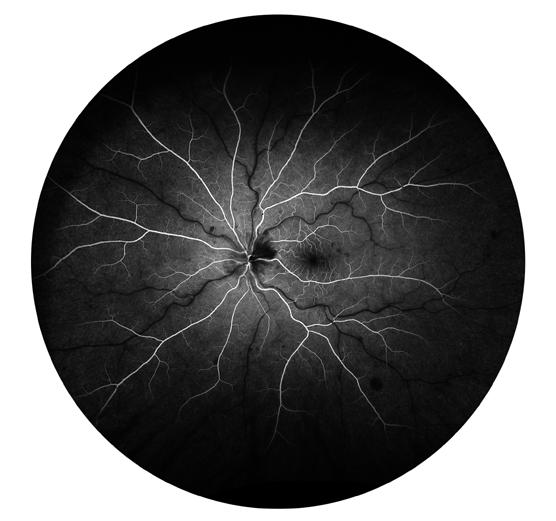

Purtscher retinopathy is often associated with blunt trauma, but may also occur in other systemic conditions like acute pancreatitis, hemolytic uremic syndrome, and renal failure where acute complementmediated leukoembolization likely contributes to the typ-

ical appearance of cotton-wool spots, retinal hemorrhage, optic disc edema, and inner retinal whitening. Affected patients also experience reduced vision acuity with possibilities of eyesight recovery, depending on the disease progression in other affected organs.1 However, the

a c d e b

Figure 1: Multimodal imaging of NHP Purtscher-like retinopathy. (a) External photographs, (b) color fundus photographs (FP), (c) spectral-domain optical coherence tomography (OCT), (d) early-phase fluorescein angiography (FA), and (e) late-phase FA of the left and right eyes of the affected macaque during the clinical eye examination at 16 years old. Abbreviations: OD, right eye; OS, left eyes. Scale bars, 200µm.

A 16-year-old female rhesus macaque (Macaca mulatta) was diagnosed with severe Purtscher-like retinopathy during a routine eye examination. Intraocular pressures were 7 and 8 mmHg for the right and left eye, respectively, but with no other anterior segment abnormalities (Figure 1a). Fundus examination and photography revealed diffuse cotton-wool spots bilaterally extending across both macula and periphery, which corresponded to the nerve fiber layer (NFL) thickening on optical coherence tomography (OCT) suggesting NFL infarction (Figures 1b and 1c). OCT also showed severe retinal edema with intraretinal and subretinal fluid which was more prominent in the right eye (Figure 1c). Intraretinal hyperreflective foci were also apparent on OCT, suggesting intracellular infiltrates that are likely inflammatory in nature. Early-phase fluorescein angiography (FA) of the right eye showed choroidal filling defects suggestive of

patchy choroidal ischemia while late-phase FA exhibited multiple foci of leakage, suggestive of increased retinal vessel permeability in both eyes (Figures 1d and 1e). The affected macaque died one month after the eye examination. At necropsy, the cause of the sudden death was attributed to left ventricular hypertrophy. Damage to the kidneys and the lungs were found with glomerulosclerosis and interstitial fibrosis in the kidneys along with tubular casts, blood, and high levels of protein found in the urine. Acute pulmonary edema was also noted. Furthermore, the tricavitary fibrinous effusion and focal acute myocardial necrosis suggested that this animal was septic although the source of infection was unknown. We hypothesize that the sepsis and renal failure were the cause of the Purtscher-like retinopathy in nonhuman primates.